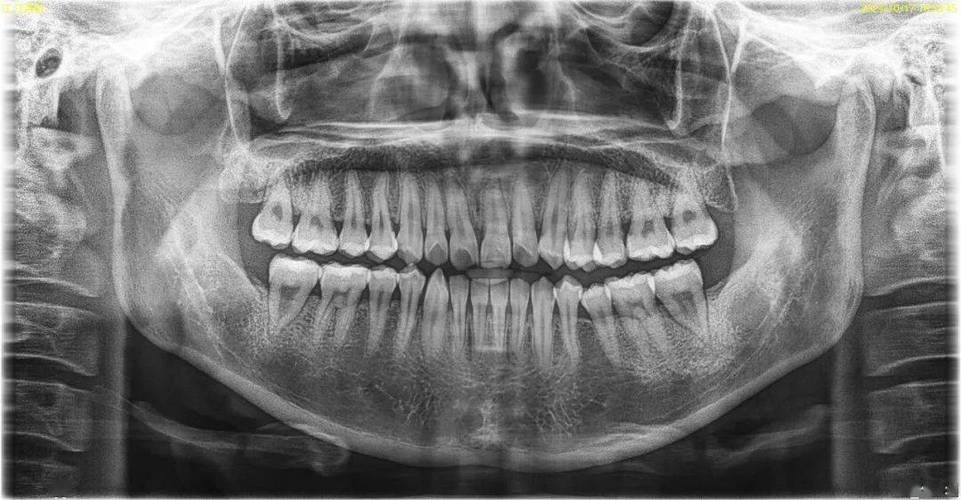

正畸治疗中,部分患者因牙齿拥挤、前突、咬合紊乱等问题需要拔除部分牙齿(即“减数”),以获得足够的间隙实现牙齿排列和咬合功能的改善,而全景片(全景曲面断层片)作为正畸减数前的基础影像检查,是医生制定治疗方案的核心依据,能全面反映口腔颌面部的重要解剖结构,为减数决策提供精准数据支持。

全景片的核心价值在于其能一次性显示全口牙齿、牙槽骨、颌骨及颌面部软组织的影像,它包含以下关键观察指标,可通过表格清晰呈现:

全景片还能识别潜在风险,如邻牙牙根吸收、囊肿、埋伏牙与重要解剖结构(如下颌神经管)的位置关系,避免拔牙时损伤神经或引发并发症,尽管全景片为二维影像,对牙根腭侧/颊侧倾斜、骨皮质厚度等细节显示不如CBCT,但其辐射剂量低、拍摄便捷、费用较低,仍是正畸减数前不可或缺的“第一道检查关卡”,可以说,全景片如同正畸减数治疗的“导航地图”,通过清晰呈现口腔解剖结构,帮助医生精准规划拔牙方案,确保治疗安全与效果,是每一位需要减数的正畸患者必做的关键检查。